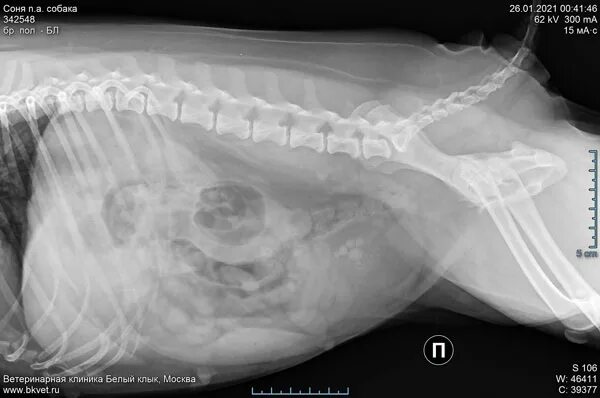

Струвитном типе мкб